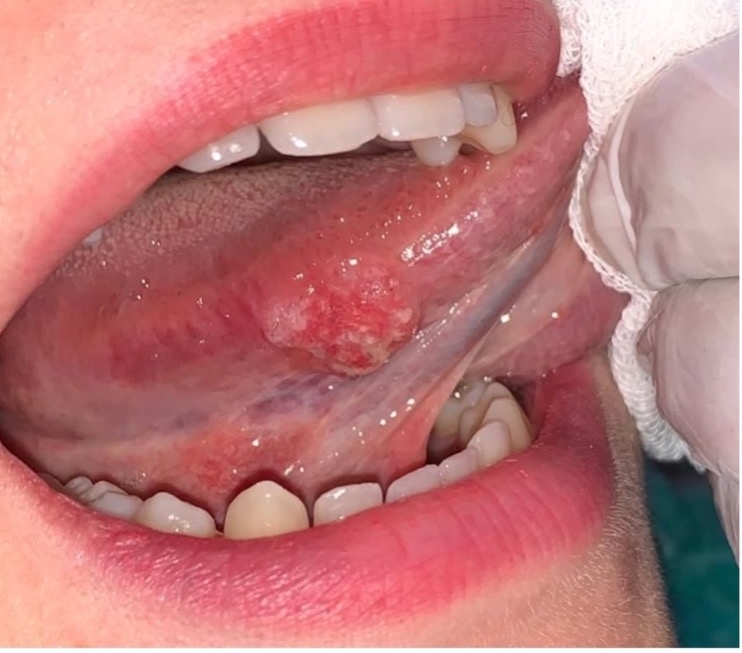

-کارسینوم سلول سنگفرشی

-علائم: زخم یا تودهای که بهسادگی خونریزی میکند و علیرغم گذشت بیش از دو هفته، بهبودی نشان نمیدهد. ممکن است با درد همراه نباشد.

-درمان: تشخیص قطعی با بیوپسی انجام میشود و درمان استاندارد شامل جراحی، شیمیدرمانی و پرتودرمانی است.

“ناحیه کف دهان، بهخصوص در افراد سیگاری و مصرفکننده الکل، مهمترین محل تشخیصی برای سرطان دهان در نظر گرفته میشود. هیچ ضایعه زیر زبان که ماهیت آن نامشخص است، نباید نادیده گرفته شود و مشاهده آن بهتنهایی کافی نیست؛ بیوپسی استاندارد طلایی تشخیص است.” (WHO)